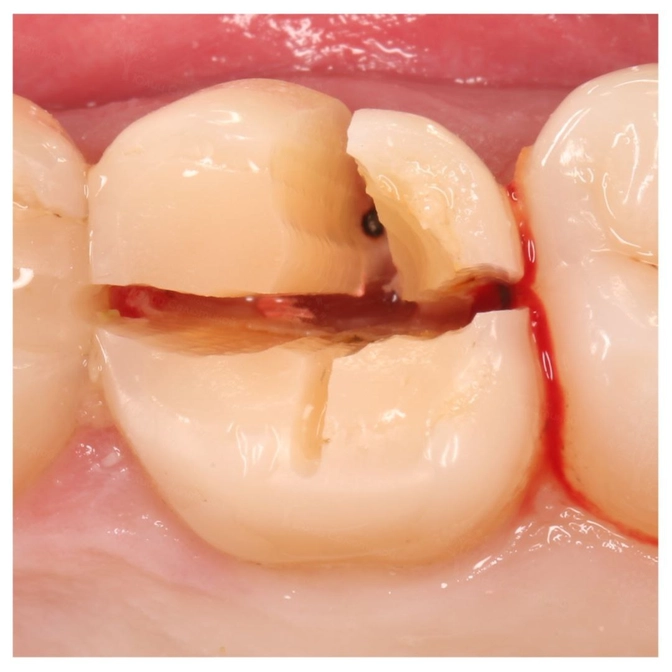

Пациент обратился с жалобой на скол зуба.

Шестой зуб был депульпирован и восстановлен большой пломбой.

Тут было прямое показание для установки коронки, потому что утеряна практически вся жевательная поверхность.

Пломба с такой нагрузкой не справилась.

Зуб раскололся пополам.

Перелом коронки.

И к сожалению, такой зуб уже не восстановить.